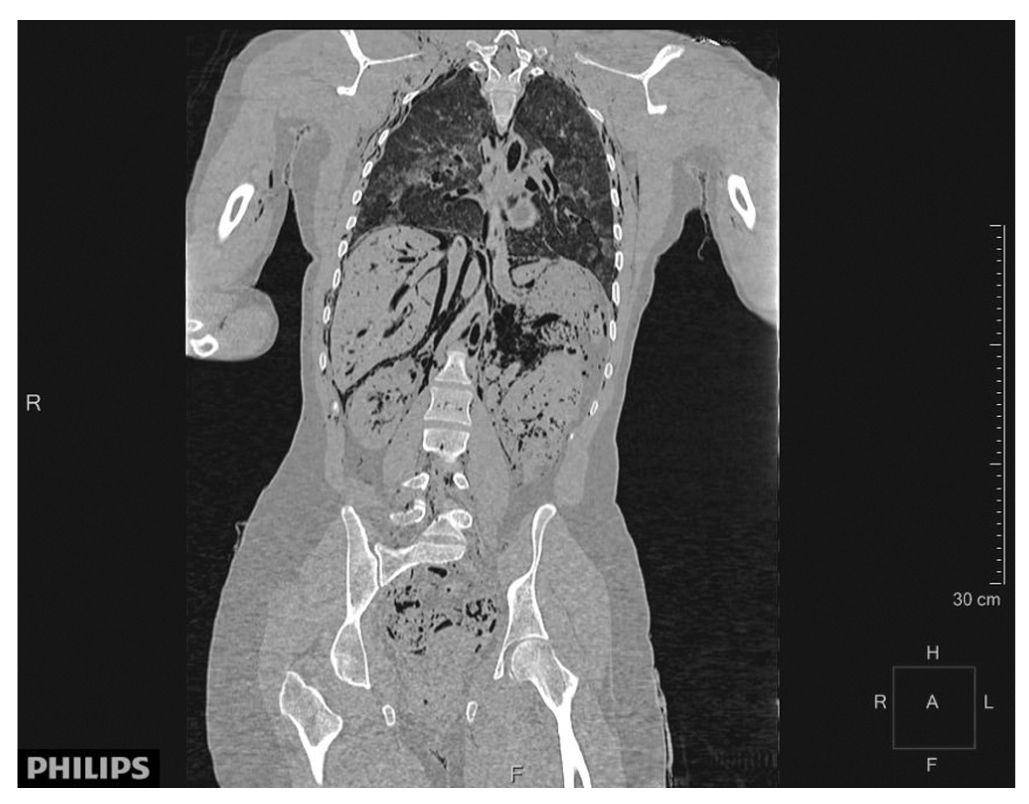

Легочная ткань с обеих сторон неравномерной воздушности с формированием картины «мозаичной перфузии» (рис. 5).

Рис. 5. Вздутие легких

В трахее, главных бронхах, субсегментарных нижнедолевых бронхах с обеих сторон — жидкостное содержимое с тотальным заполнением трахеи и главных бронхов.